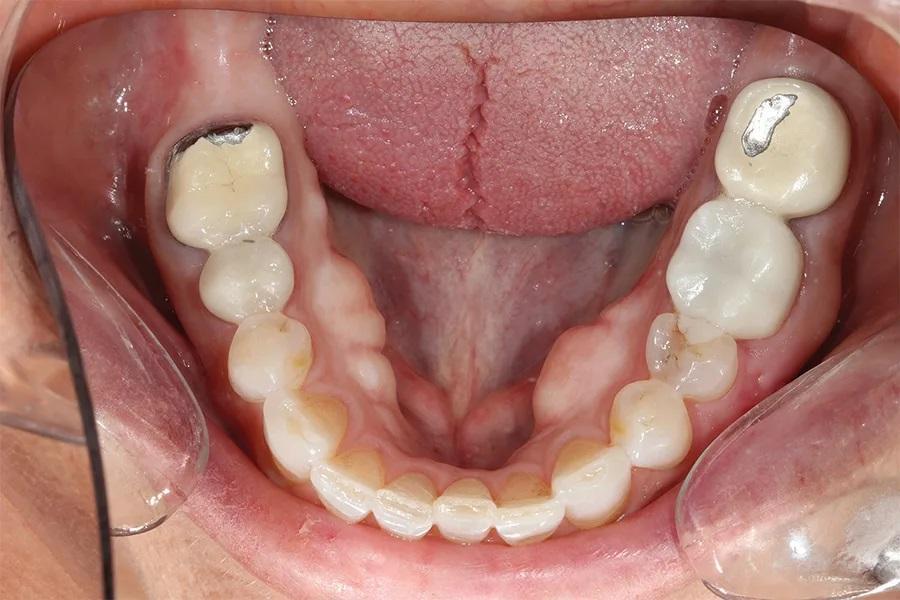

Биомеханический статус: Фарфор был истерт до металла на зубах 37 и 46. Временная конструкция на имплантате в области зуба 15 была сломана. Эрозивные поражения отмечались на зубах 13, 12, 23, 33 и 43. На зубе 17 имелась разрушенная амальгамовая пломба, а на зубе 35 — сомнительная реставрация (фото 6).

Фото 6. Окклюзионный вид нижней челюсти до лечения, демонстрирующий износ режущих краев и существующих металлокерамических коронок.